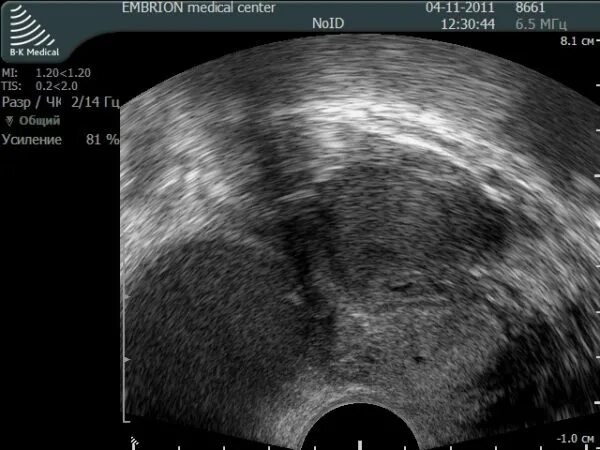

Аденомиоз диффузные изменения